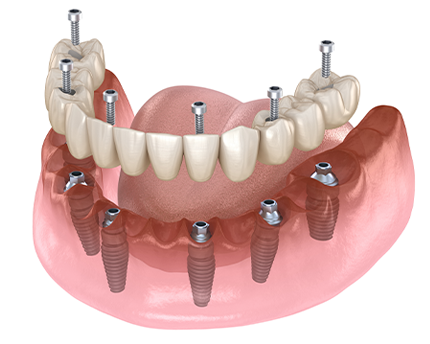

전체임플란트란

치아가 빠진 상태로 오래 방치된 잇몸은 서서히 체내로 흡수되게 됩니다.

이런 잇몸은 임플란트를 식립하기에 부족하고 약해져 뼈이식 수술이 필요하게 됩니다. 또한 심한 충치, 잇몸질환으로 손상된 잇몸도 임플란트 시 뼈이식 수술이 필요할 수 있습니다.

전체임플란트 치료핵심POINT 3

건강한 잇몸뼈전체임플란트는 다수의

임플란트를 식립하기 때문에

건강한 잇몸뼈를 찾는것이

중요합니다.

전체임플란트는 구강 전체에 대한 정확한 이해가 필요한 치료입니다.

전체임플란트는 치아가 전혀 없거나 모든 치아를 발치하게 된 경우

치아전체를 임플란트로 수복하는 고난이도의 시술입니다.

단순히 많은 임플란트를 식립하는 것이 아닌, 자연치아과 같은

정확한 교합, 잇몸과 조화로운 비율, 수술시 환자에게 체력적으로 무리가

되지 않는 안전함 등을 고려하여 환자에게 맞춘 치료가 필요합니다.